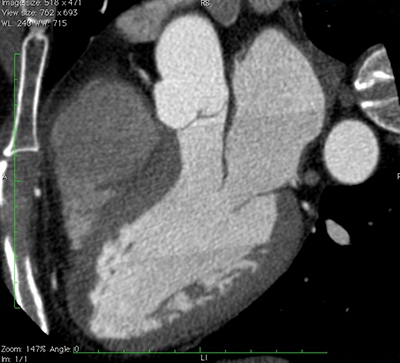

Cardiac Computed Tomography (CT) Scan

Cardiac computed tomography (CT) is an imaging process that uses X-rays to show details of the arteries and veins of the heart. The images are used to determine whether plaque or calcium deposits are present in your blood vessels and whether they are causing a blockage.